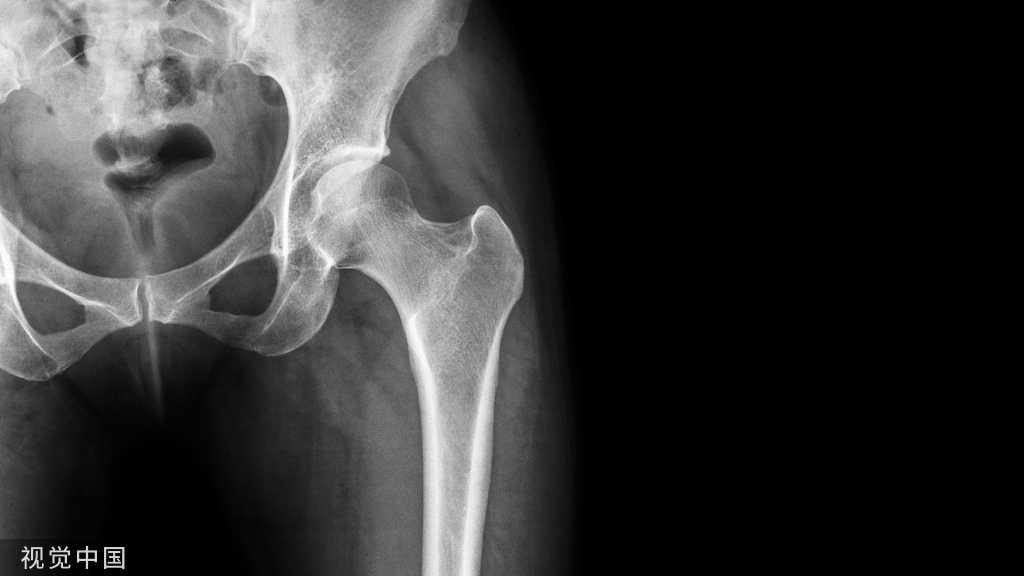

下肢牵引术应用比较广泛,从股骨颈骨折,转子间骨折,股骨骨折,到胫腓骨骨折等,都需要用到牵引。对于下肢骨折,两种牵引方法均可应用:皮牵引用于临时固定或术前稳定;而骨牵引多用于手术禁忌患者的治疗性措施。

Buck's(图 7)或 Russell's(图 8)皮肤牵引:在股骨骨折,转子间骨折或髋部骨折中应用广泛,下肢骨折使用皮牵引一般不能达到复位效果,但是可以在一定程度上减轻疼痛和保持局部肢体长度。

除此之外,在严重髋臼骨折股骨头中央型脱位患者中,可以沿股骨颈轴线方向进行牵引,减少股骨头髋臼中央的压力,并尽量获得一定程度上复位(图 13)。